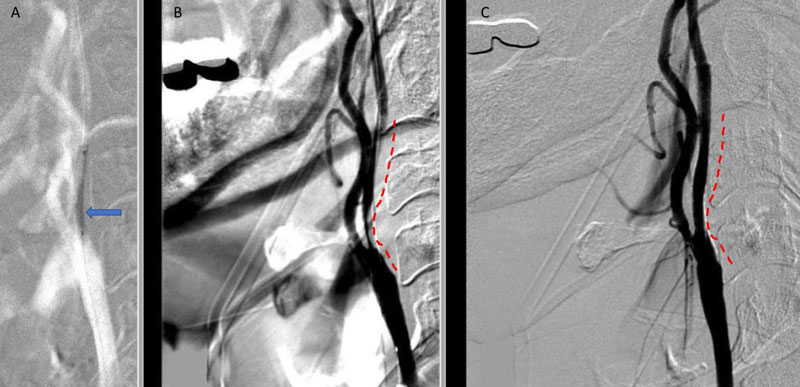

On admission, her initial CT scan was negative for stroke or hemorrhage, however a CTA demonstrated severe high grade 99% stenosis of the right Carotid bulb (ICA) with markedly diminished caliber of the cervical intracranial carotid artery secondary to calcified atherosclerosis without evidence of dissection (Figure 1).

Figure 1. A and B) CTA demonstrating severe ICA 99% stenosis (dotted) with flow-reduced diminution relative to the left ICA (red arrows) and distal plaque extension to C2 level.

Catheter cerebral angiography was then performed which demonstrated the 99% stenosis with distal vascular collapse and extension of the plaque superiorly into the mid third of the cervical right ICA (Figure 4). Interrogation for collaterals from the left ICA and posterior circulations demonstrated very small and minimal contributions from the anterior communicating artery and posterior communicating artery of the Circle of Willis.

Figure 4. A) DS Angiogram demonstrates severity and extent of plaque to C2-3 level (blue). B) And marked delay of ICA perfusion (yellow) relative to ECA branches (green).